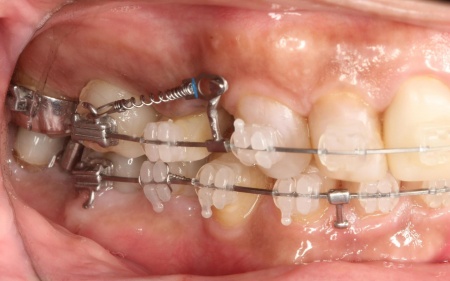

まずは、口腔内全体の矯正治療から開始します。

上顎は左上の歯が欠損していたため、左右のバランスを整える目的で、右上の歯(第1小臼歯)を抜きました。

その後、ワイヤー矯正とクローズドコイル(バネの装置)を使ったスピード矯正を行い、前歯を後方に移動させます。

下顎は残根も利用しながら、矯正用の小さなネジ「テンポラリーインプラント(インプラントアンカー)」を顎の骨に埋め込んで固定源とする方法も併用し、歯を移動させました。

矯正期間中は定期的に装置の調整を行い、歯の動きや噛み合わせの変化を確認しながら治療を進めています。